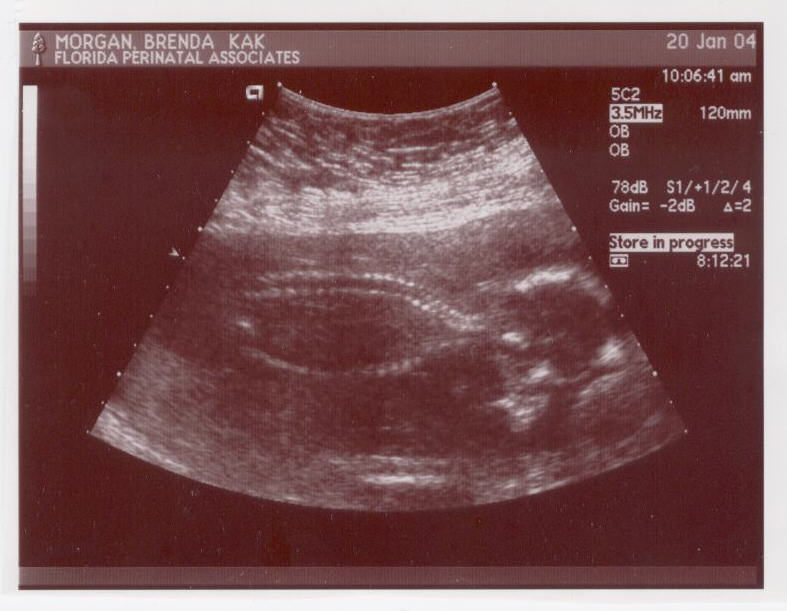

18 weeks |

01/20/2004 |

Level 2 Ultrasound. The baby's heartbeat was 133, and boy was she feisty. She kept twisting and turning when they needed to see her heart and all. She's 10 ounces, and seems to be really long. IT'S A GIRL! |